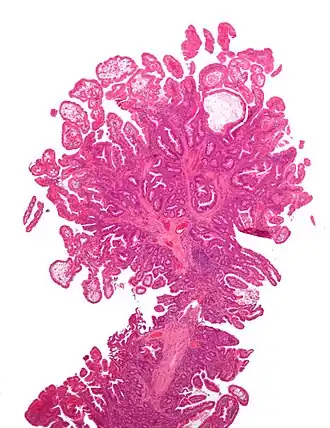

Le syndrome de Peutz-Jeghers (SPJ) est une maladie génétique rare caractérisée par le développement de polypes hamartomateux dans le tube digestif.

Les personnes atteintes de Peutz-Jeghers développent des polypes localisés au niveau de l’intestin grêle (70-90 %), du côlon (50 %) et de l’estomac (25 %)[1] principalement, qui ont une tendance à la cancérisation. Ces personnes ont donc un risque accru de cancers gastro-intestinaux, tel que le cancer du pancréas, de l'estomac, de l'intestin grêle et du colon, mais ont aussi un risque majoré de cancers extra-digestifs tel que le cancer du sein, du poumon, de l'utérus, des ovaires et des testicules. Ces polypes, à la base bénins, peuvent entrainer des complications tels qu’un saignement de ces polypes (responsables d’anémie ferriprive lorsqu’ils sont chroniques), une occlusion intestinale, un prolapsus rectal, une hémorragie digestive sévère avec anémie secondaire, et une invagination.

Comme mentionné, le Peutz-Jeghers possède des manifestations physiques externes (via les macules présentes sur les muqueuses) et internes (via les polypes hamartomateux et le risque accru de cancers invasifs dû à la délétion/mutation du gène suppresseur de tumeur).